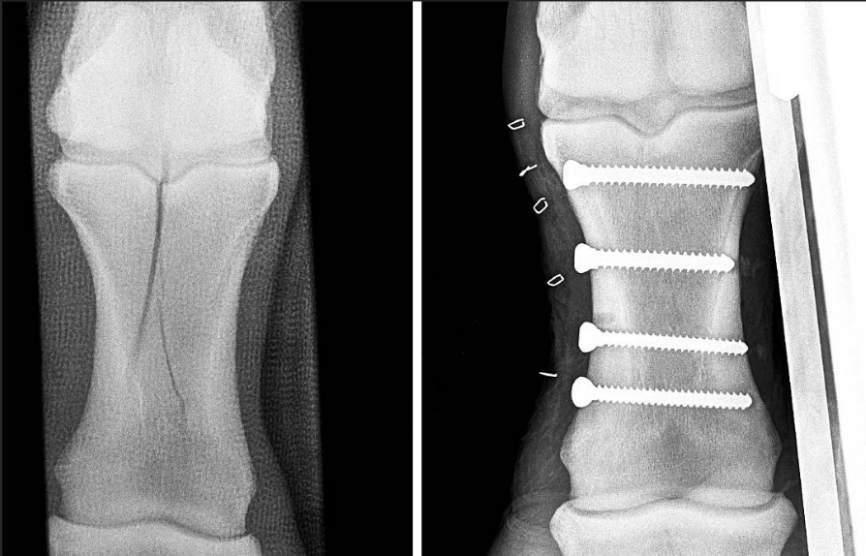

因此,骨折手术的本质是在帮助断端复位并维持稳定的状态——无论是采用内固定(如钢板、钢钉)还是外固定(如石膏、夹板),目的都是为了创造一个稳定的愈合环境。

马匹骨折后,通过钢钉固定骨碎片